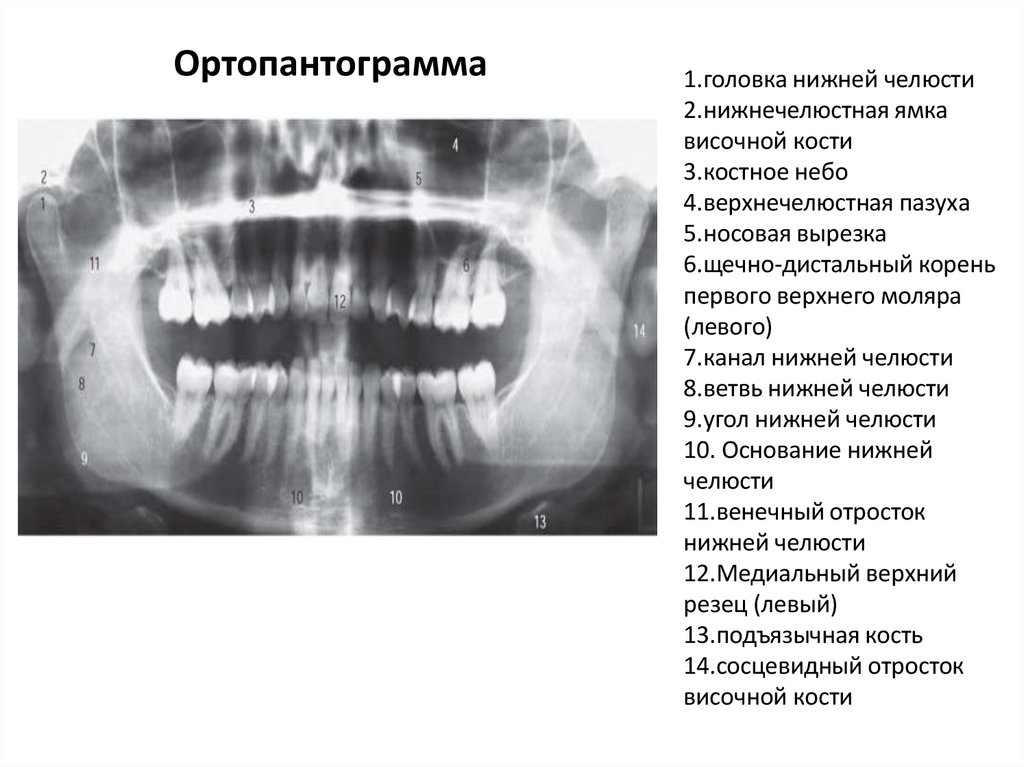

Ортопантограмма

1.головка нижней челюсти

2.нижнечелюстная ямка

височной кости

3.костное небо

4.верхнечелюстная пазуха

5.носовая вырезка

6.щечно-дистальный корень

первого верхнего моляра

(левого)

7.канал нижней челюсти

8.ветвь нижней челюсти

9.угол нижней челюсти

10. Основание нижней

челюсти

11.венечный отросток

нижней челюсти

12.Медиальный верхний

резец (левый)

13.подъязычная кость

14.сосцевидный отросток